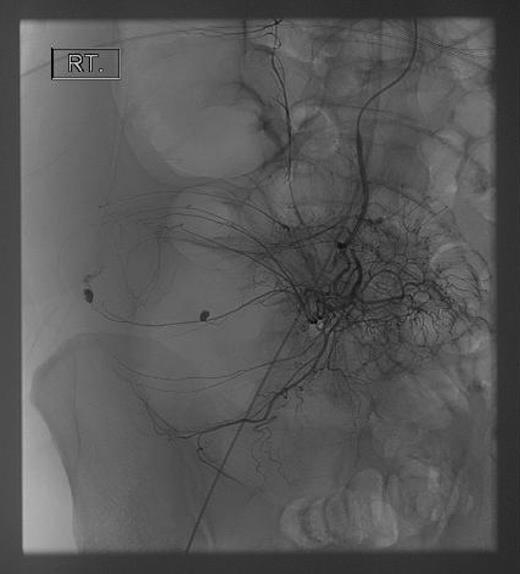

Seventy-two hours after starting his anti-tubercular therapy, he took a turn for the worse and was transferred to the ICU for ventilatory and inotropic support. He had ∼1 l of bleeding per rectum and dropped his haemoglobin (Hb) from 140 to 65 g/l. An oesophagogastroduodenoscopy showed no cause for upper GI bleeding. A CT abdomen + pelvis with contrast was performed, which showed a large (20 cm) inflammatory caecal mass with a moderate amount of intra-abdominal free fluid (Fig. 2). Selective angiography of the superior mesenteric artery demonstrated the bleeding point in the caecum and this was embolized superselectively with coils (Fig. 3).